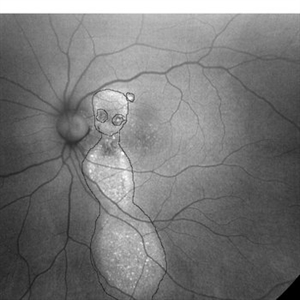

Chronic CSR - Dancing doll

37-year male with chronic CSR

Photographer: Harsh Vardhan Singh

Imaging device: Zeiss clarus 700

Condition/keywords: autofluorescence imaging, Central Serous Chorioretinopathy (CSR), fundus autofluorescence (FAF), idiopathic central serous choroidopathy (ICSC)